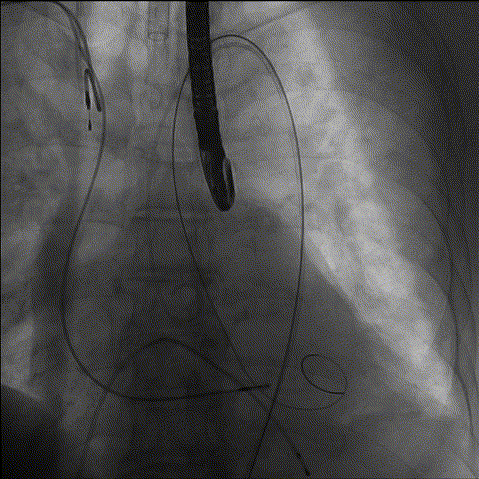

3、预扩

综合各项评估,手术团队采取右侧为主入路,鉴于左冠风险,决定先用10mm球囊,再用22mm球囊预扩,植入Evolut PRO 29mm瓣膜、Cusp Overlap标准6步植入法、20Fr导引鞘。